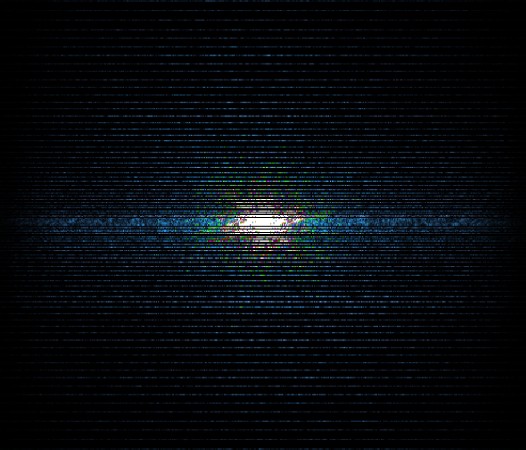

In the example below, only one fifth of the required MR radiofrequency signals is recorded. This results in a five times faster acquisition, with a subsampled k-space (top left) and inherent image artifacts after standard reconstruction (top right).

K space